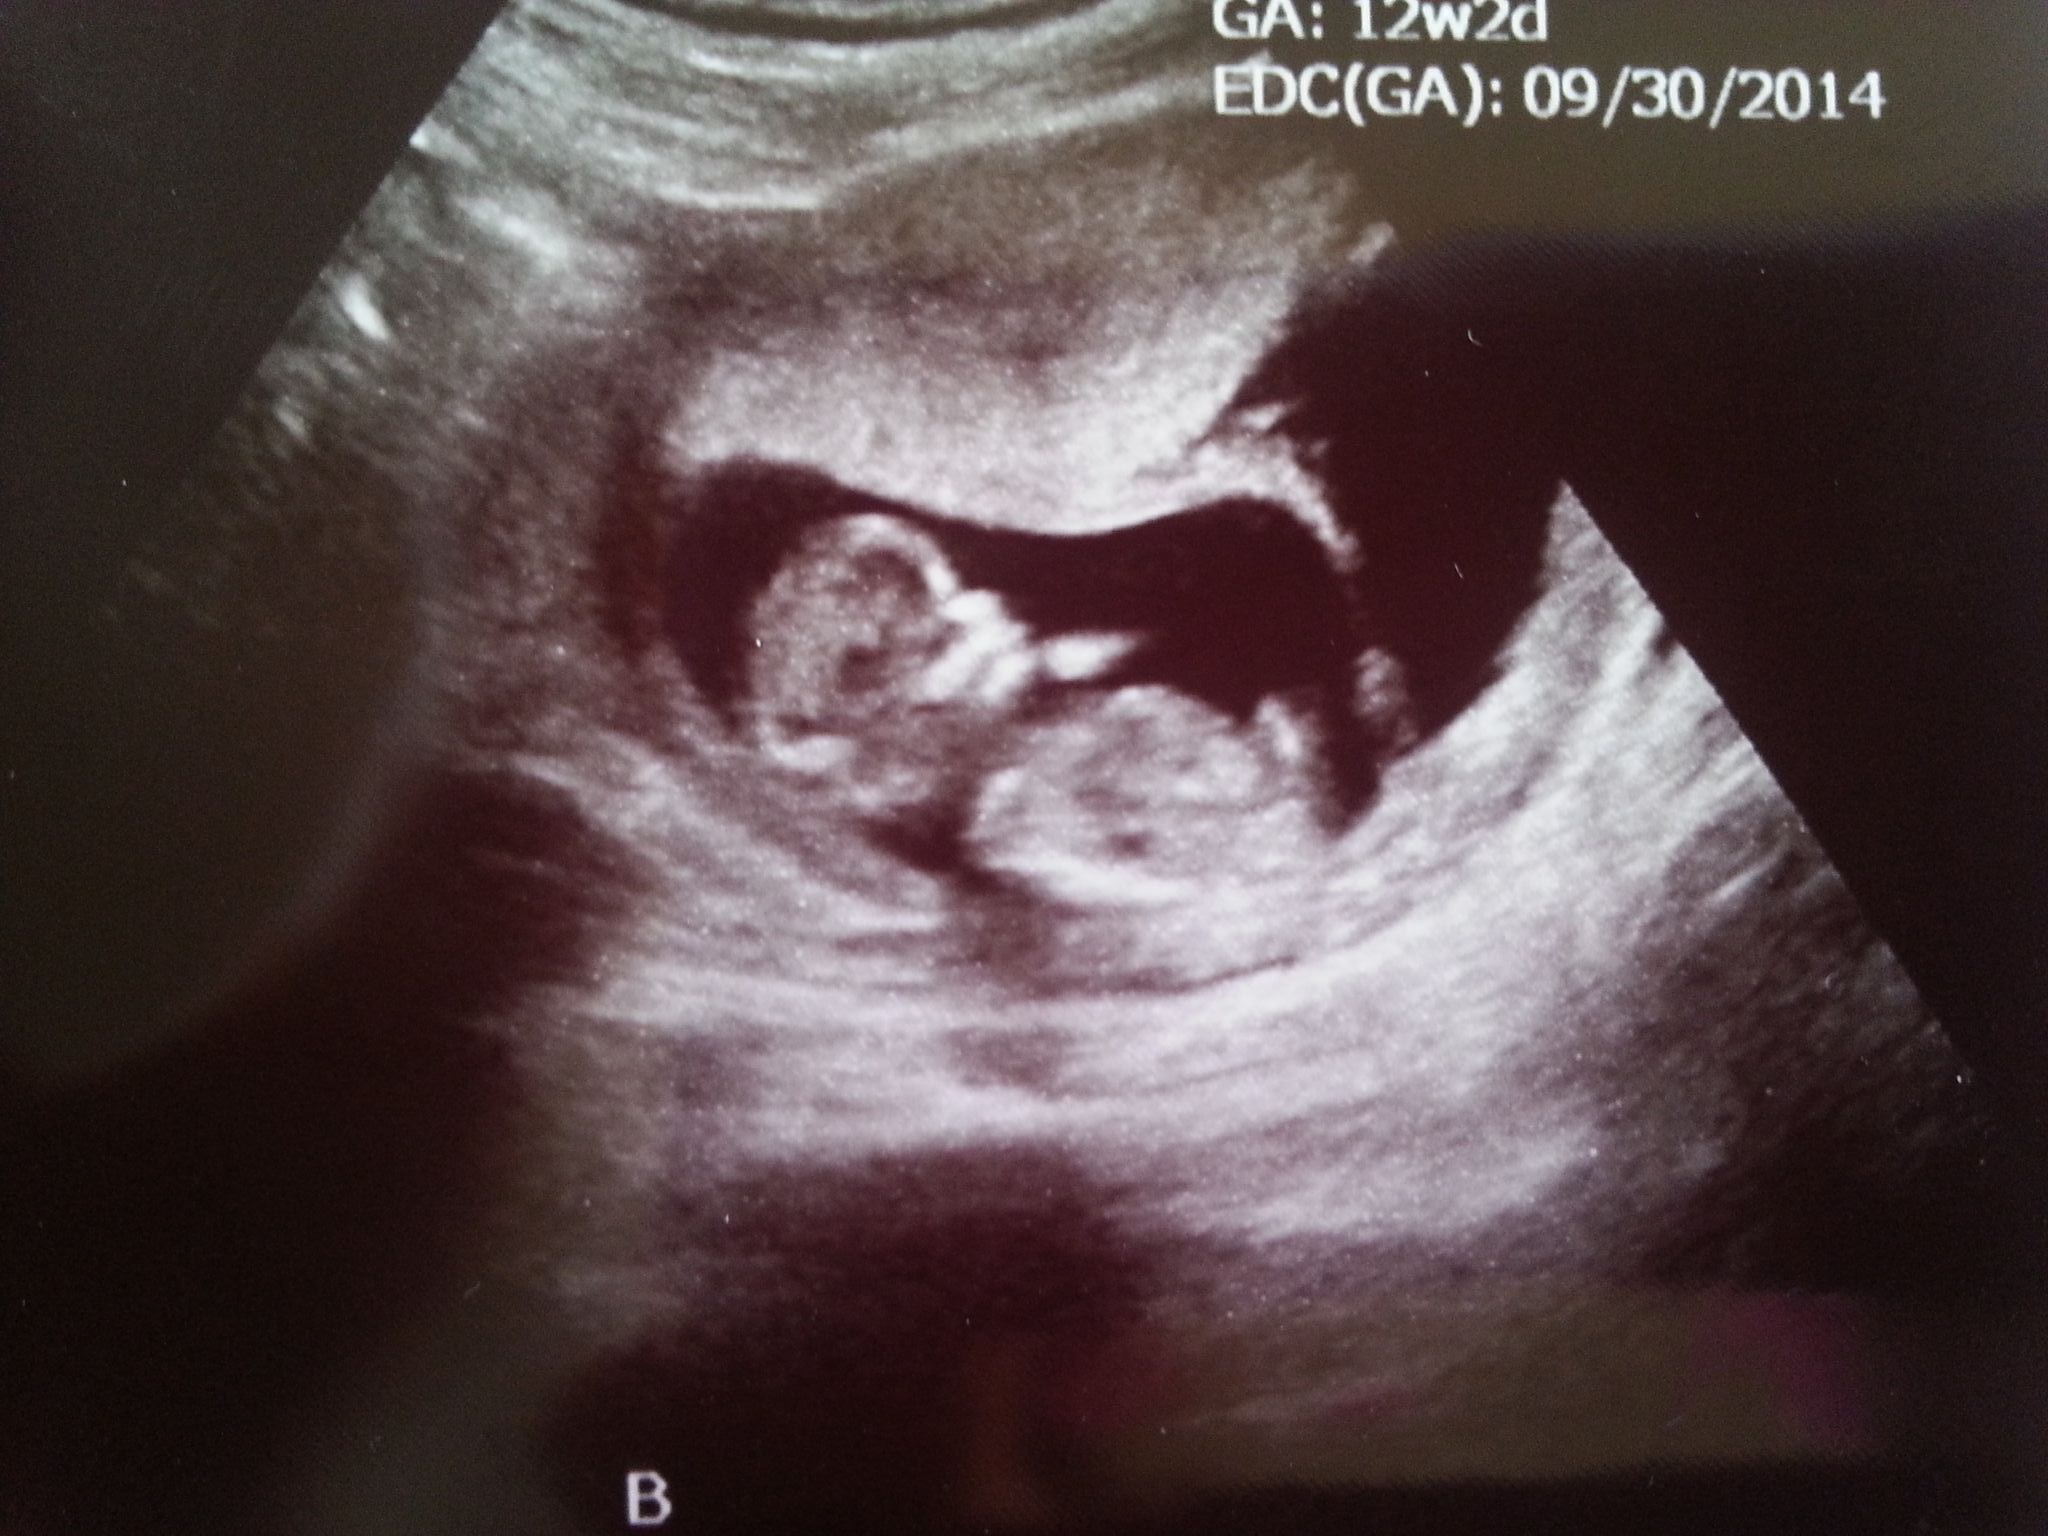

Attachment 18082Attachment 18083Attachment 18084Attachment 18085

We were in for the biggest shock to date when our 12 week, 2 day NT scan showed TWINS!!! We already have a 3 year old super sweet little boy, both of us are really hoping for a girl... but our tech thought boys??